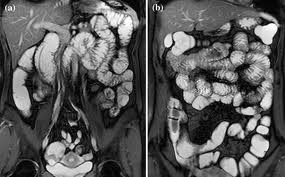

МРТ желудка и кишечника является методом исследования внутренних органов брюшной полости, после ее проведения получают снимки и трехмерную модель органа, подвергающегося исследованию, а также расположенных рядом тканей. Метод основан на поведении ядер атомов водорода, помещенных в магнитное поле повышенной мощности. Процедура считается безопасной (если нет противопоказаний), т.к. вредное облучение отсутствует, ее можно делать подряд несколько раз.

В результате проведения исследования получают снимки, на которых отображаются органы брюшной полости и кишечник, их состояние. Метод сканирования позволяет провести исследование самых труднодоступных отделов кишечника с целью обнаружения полипов, выявления онкологии и отдаленных метастазов, помогает оценить размеры опухоли и состояние расположенных рядом органов и прилежащих тканей. Во время послеоперационного периода с помощью МРТ есть возможность контролировать активность процесса воспаления.